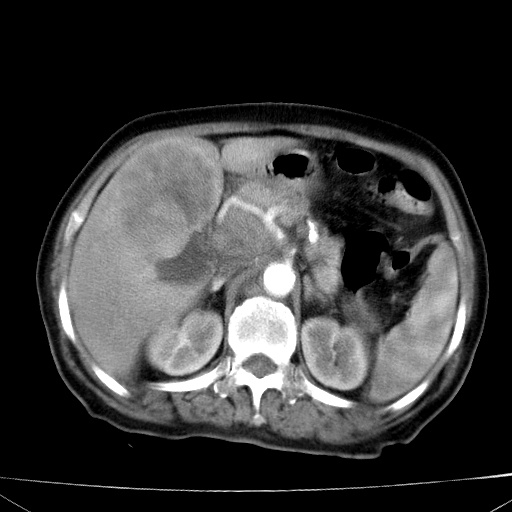

网站人气太旺!昨天的帖子就沉到海底,只好再发贴!ct18338:女 78岁,肝胆病变,已增强,再会诊!原帖链接:http://www.radida.com/bbs/forum.php?mod=viewthread&tid=50032

1)考虑胆囊癌侵犯肝脏并肝门区、腹膜后及右侧膈角后淋巴结转移。2)肝左叶近肝顶部囊肿。3)肝左叶肝内胆管结石。4)左肾近下极囊肿。

1、胆囊癌侵犯肝脏并腹腔及腹膜后淋巴结转移。

2、肝左叶外侧段囊肿。

3,肾囊肿